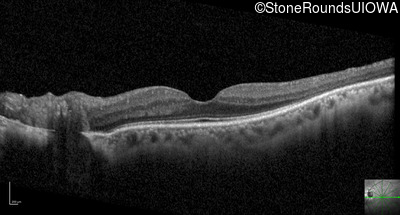

Optical Coherence Tomography - Right - 20/16

Exemplar / OCT Stack